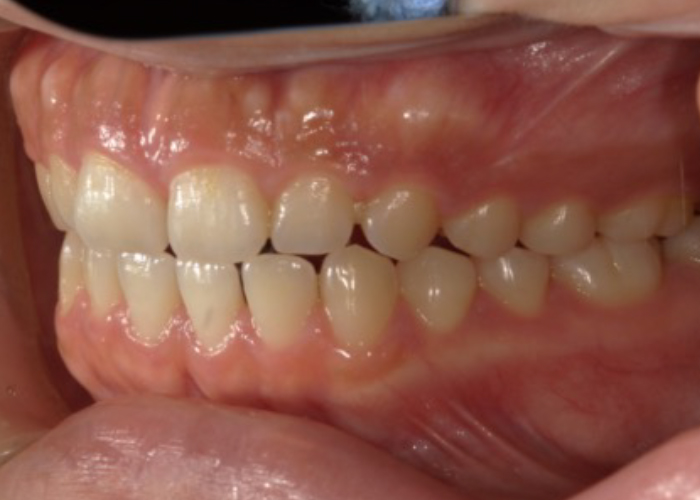

ガタガタで噛みにくい

八重歯と見た目をきれいにしたい